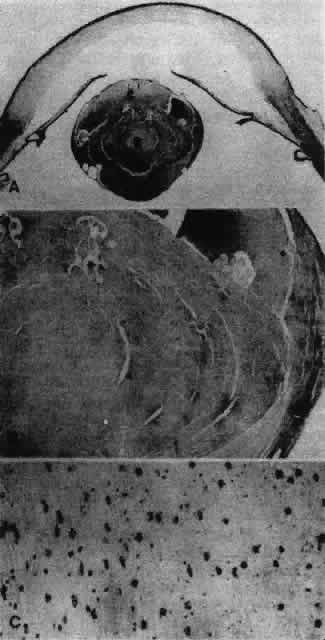

Other opacities that fall under the category of capsulolenticular cataracts are the polar cataracts. In this case, the opacities are situated at either pole of the lens and generally involve only the superficial cortical area. The relatively common anterior variety assumes a number of forms but is typically plaquelike and circumscribed. The size of the opacity may vary from a small dot to one that occupies the entire pupillary region. Because it may have a laminate appearance, it has also been called a pyramidal cataract. Similar opacities are observed in children who have had corneal ulcers during infancy. The fact that the fetal nucleus of the lens is not involved suggests an occurrence relatively late in intrauterine life. Occasionally, an opacity might be seen above the previously incurred derangement separated by an apparently normal lenticular zone, producing the so-called reduplicated cataract. In this case, it is believed that, following an initial disturbance, normal fibers are deposited, followed later by a new, sometimes more severe disturbance that produces a second region of opacification. There are a number of variations on this theme, and such opacities may assume myriad possible forms. It may be significant that these opacities are often associated with a strand or strands of pupillary membrane that bridge the iris (in the region of the collarette) to the polar cataract.181–183 Similar adhesions to the pupillary margin have been noted. Another observation has been that these cataracts are often associated with signs of keratitis, most notably corneal opacification. It is interesting that, histologically, the changes are similar to those observed in the adult human lens following corneal ulceration.177–180 The polar cataract is typically associated with a hyperplasia of the epithelium and a great deal of necrosis of lens fibers in the subepithelial area.184 Multistratification of the epithelium occurs as the cells fill a depression left by the necrotic fibers (Figs. 36 AND 37). The cells become spindle-shaped and produce PAS-positive material. Contrary to a long-held but erroneous notion, the plaque thus formed does not represent a metaplastic transformation of epithelial cells into fibroblasts.185 The plaque is often undermined by normal cuboidal epithelial cells and is eventually surrounded by capsulelike material (see Figs. 36 AND 37). The most reasonable explanation of the basis of this anomaly is the development of intrauterine inflammation. Although it has been suggested that the anterior polar cataract may be the result of a persistent vascular tunic that interferes with nutrition, the counterpart, the posterior polar cataract, need not be associated with hyaloid remnants, yet the histologic picture is quite similar.

Fig. 36. Photomicrographs of the development of anterior subcapsular cataract. A. The beginning of multistratification of the anterior epithelium, owing to localized hyperplasia of the lens epithelial cells. B. Further stratification of the epithelium, with denucleation occurring in some of the cells. C. The final stage of cataract formation showing the so-called fibrous plaque (F), bounded on the anterior and posterior sides with capsule material. Beneath the posterior capsule (C) a newly formed epithelial population can be seen (E). (Yanoff M, Fine BS: Ocular Pathology. New York, Harper & Row, 1975)

Fig. 37. Development of anterior polar cataract: schematic illustration of the sequence of events described in Figure 36. (Font RI, Brownstein S: A light and electron microscopic study of anterior subcapsular cataracts. Am J Ophthalmol 78:972, 1974)